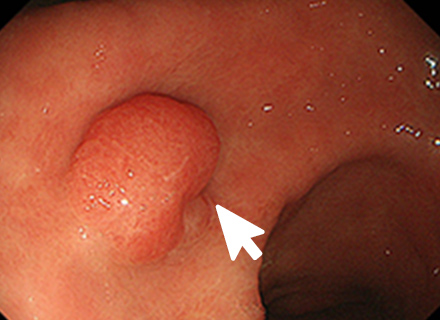

内視鏡治療の対象となる胃がんは、病変が一括で取れる部位と大きさであり、リンパ節転移の可能性がほとんどないほぼ粘膜内にとどまっていると診断された早期胃がんになります。

内視鏡的治療が外科手術に比べ優れた点は、入院期間が短い上に、おなかに傷がつかず、大きな併発症がなければ退院後の食生活、社会生活に支障がないことです。劣っている点は、切除した組織の状態によっては遺残病変の有無が確認困難な場合があり、将来再発する可能性があることや、切り取った病変の組織検査の結果、局所にがん細胞が残っている可能性がある場合や、がんがリンパ節に転移している可能性があると判断された場合は、さらに外科手術が必要になることです。

内視鏡を使った早期胃がんの治療法には、内視鏡的粘膜切除術(EMR)と内視鏡的粘膜下層剥離術(ESD)の2種類があります。

内視鏡的粘膜切除術:EMR(Endoscopic mucosal resection)

スネアと呼ばれる金属の輪を病変部に引っ掛け、高周波電流を流して病変を切り取ります。EMRは、治療が比較的短時間ですみますが、一度に切り取ることができる病変の大きさは、スネアの大きさ(約2cm)までと制限があります。

内視鏡的粘膜下層剥離術:ESD(Endoscopic submucosal dissection)

専用の処置具を使いより広範囲に病変を切り取ることが可能な治療法です。切り取られた病変は、最終的に顕微鏡でその組織の様子が確認されます(病理検査)。この方法では、大きな病変をひとかたまりで取り、病理検査でより正確な診断を行うことができます。

ESDは大きな病変も一括して切除可能ですが、手技が煩雑で時間がかかり、出血や穿孔などの併発症が生じる場合があります。ほとんどの場合内視鏡的に止血可能ですが、稀には輸血、開腹手術などを要することがあります。

大腸ポリープまたは早期大腸がんの内視鏡治療

良性のポリープや早期がんの中でも粘膜だけにとどまっているもの、粘膜下層へわずかに広がっているものが内視鏡治療の適応となります。 小さなポリープに対しては、鉗子でつかみながら高周波電流を用いて病変の根もとを焼き切ります(ホットバイオプシー)。 茎のあるポリープに対しては、輪の形のスネアを茎の部分でしめ、高周波電流を用いて切断します(ポリペクトミー)。 茎のない病変に対しては、内視鏡的粘膜切除術(EMR)や内視鏡的粘膜下層剥離術(ESD)などを行います。